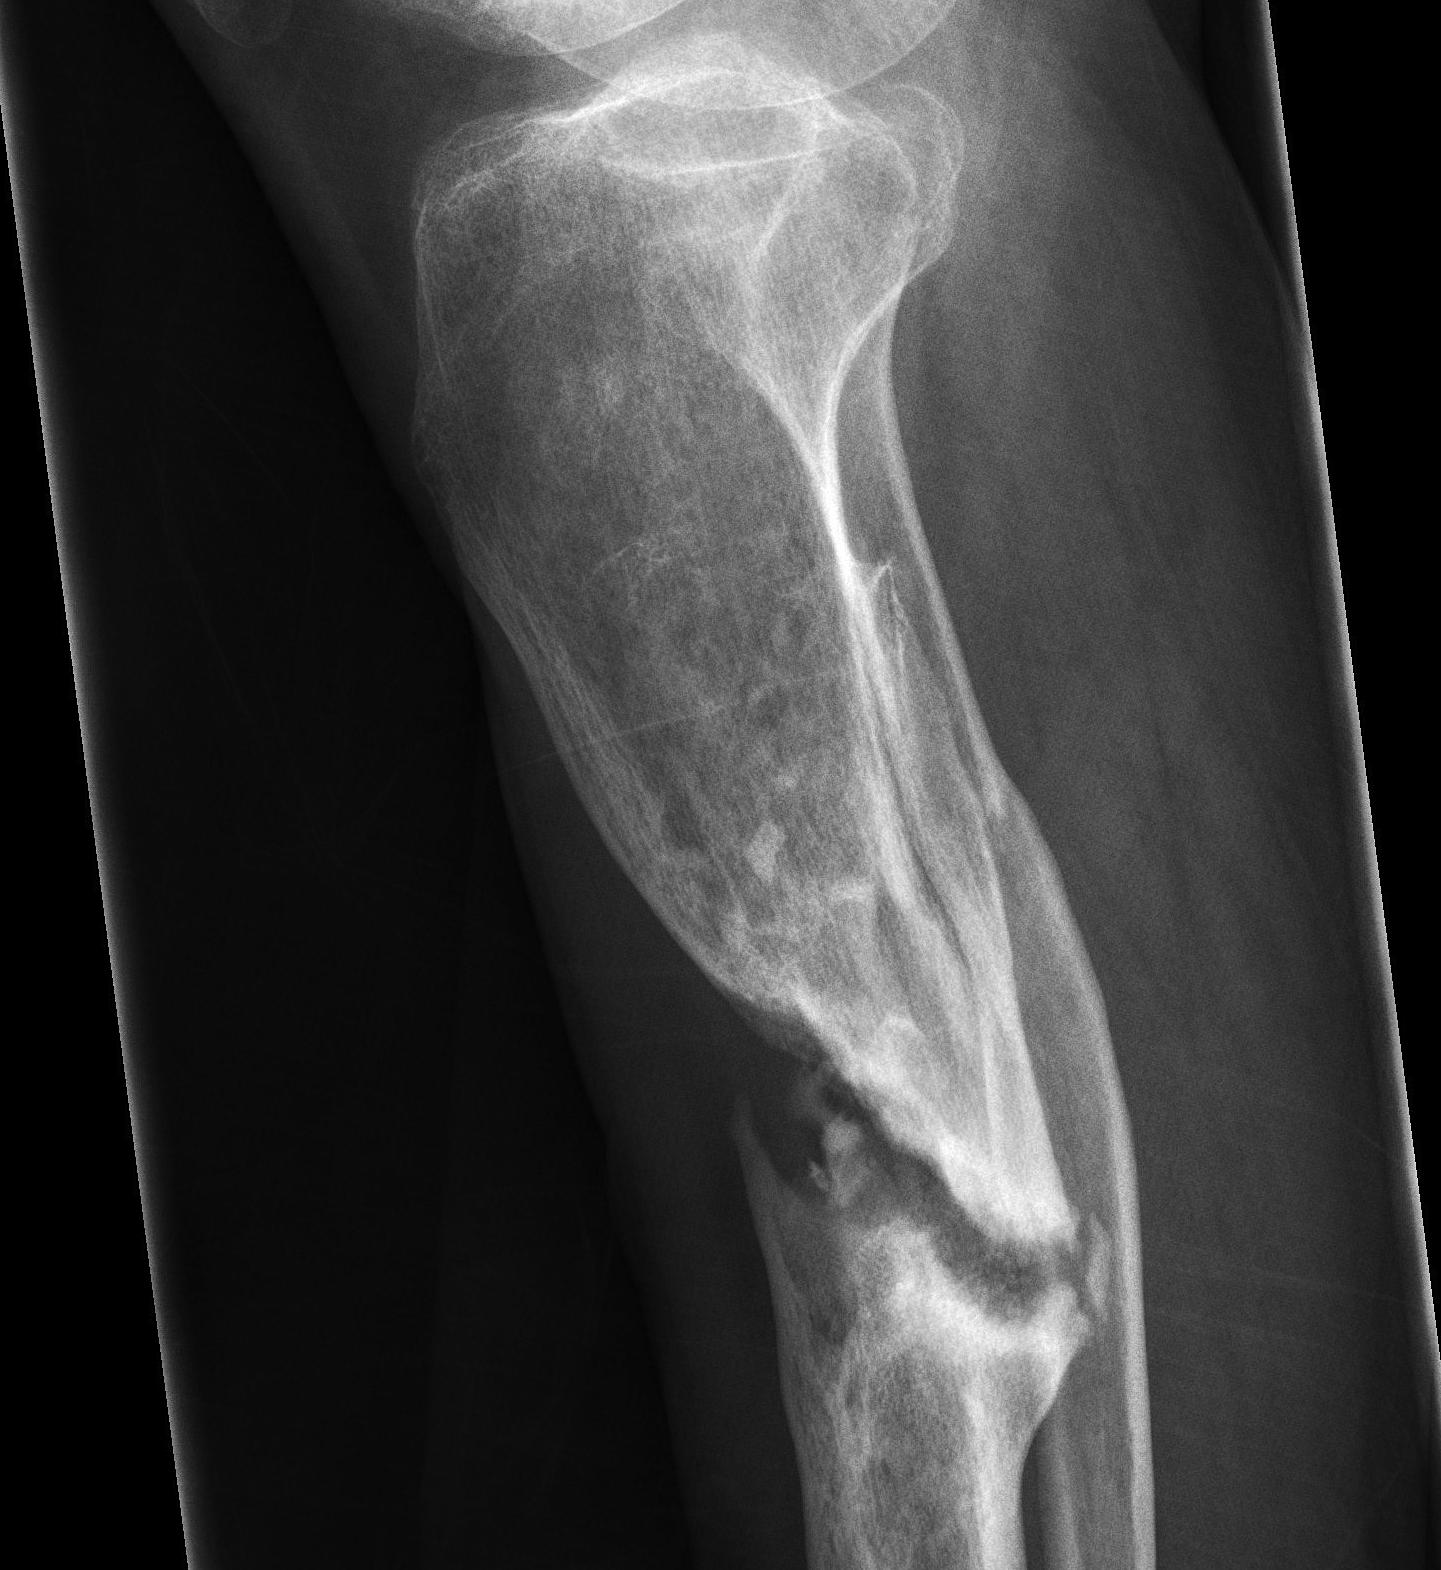

Tibial Hypertrophic Nonunion

B.  Oligotrophic

- minimal callous

- still have adequate blood supply

- due to inadequate contact between fracture surfaces

Tibial Oligotrophic Nonunion

C.  Atrophic

- no callous

- deficient biology, adequate stability (too adequate)